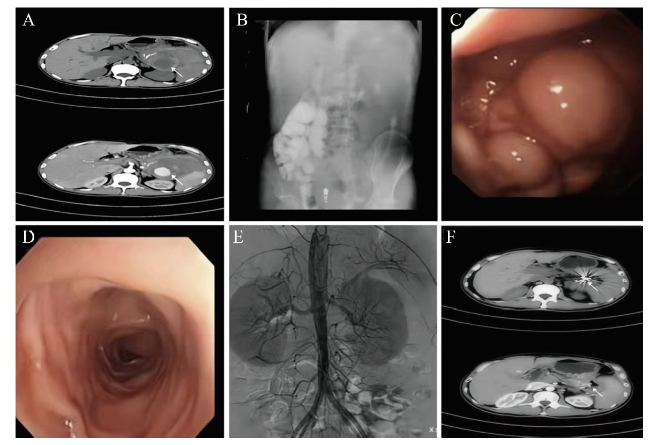

2020年6月18日MRI扫描提示胰腺萎缩,主胰管扩张,脾门处见团块状异常信号影,约5.5 cm×5.8 cm×5.7 cm,T1WI、T2WI上病灶呈高低混杂信号,DWI高b值病灶中央弥散明显受限;增强扫描病灶中央明显强化,病灶与脾动脉相连,左肾受压,脾门部见迂曲血管影,脾脏增大,实质内未见异常信号影及强化灶,脾周见少量长T1长T2液体信号影;考虑脾假性动脉瘤伴血栓形成可能大。2021年3月17日全腹部CT平扫+增强提示脾门下方可见混杂密度团块影,约8.8 cm×6.9 cm,其内可见结节状致密影,增强后可见结节状明显强化,强化程度同血管一致;脾门处和肝门部可见迂曲血管影;脾脏体积增大,周围可见少量积液;胰腺体积缩小,其内可见散在结节状致密影;考虑脾假性动脉瘤伴血栓形成可能(图1A)。结肠碘佛醇造影示结肠脾曲管腔不规则狭窄,管壁僵硬,黏膜破坏,并隐约可见结节状充盈缺损,余段结肠显影良好,结肠带对称、规整,未见明显扩张及梗阻征象,升结肠及横结肠内见较多内容物影,黏膜显示欠佳(图1B)。胃镜示胃底及相邻胃体上部前后壁、靠后壁的部分大弯可见黏膜呈静脉瘤样隆起;胃体下部小弯侧胃黏膜皱襞消失(图1C)。肠镜示进镜到达脾区,进镜阻力大无法继续进镜,见肠腔内大量淡红色血性粪汤影响观察,所见肠黏膜光滑,血管纹理清晰,结肠袋规整,腔内未见溃疡及新生物(图1D)。

图1 一例胰源性门脉高压伴脾假性动脉瘤并结肠瘘患者影像学检查及胃镜图

注:A为CT显示脾门下方混杂密度团块影(白色箭头);B为结肠造影显示脾区可见斑片状高密度影;C为胃镜显示胃底静脉曲张;D为肠镜所见肠黏膜光滑,血管纹理清晰,结肠袋规整,腔内未见溃疡及新生物;E为介入术中所见;F为术后2个月复查CT,原脾门处团块已基本消失(白色箭头)。

初步诊断:消化道出血。入院后对患者进行一系列支持治疗,包括止血、输血、补液、维持水电解质平衡等,患者于2021年3月25日夜间再次便血,量大,患者精神稍差,于2021年3月25日在放射介入室急诊行消化道造影及出血动脉栓塞术,术中脾动脉主干可见巨大囊肿影,造影对比可见对比剂呈喷射状流入囊腔内,考虑为假性动脉瘤,与患者及家属沟通后行脾动脉栓塞术,造影复查示脾动脉中段闭塞,假性动脉瘤消失(图1E)。术后辅以抗感染、护胃、止痛、补液、营养支持及输血等对症处理,术后患者未再解血便,解黄色成形便,腹痛缓解。最终诊断:考虑慢性胰腺炎伴胰源性门脉高压,并发脾假性动脉瘤伴消化道大出血。术后2个月复查CT示脾动脉瘤已消失(图1F)。